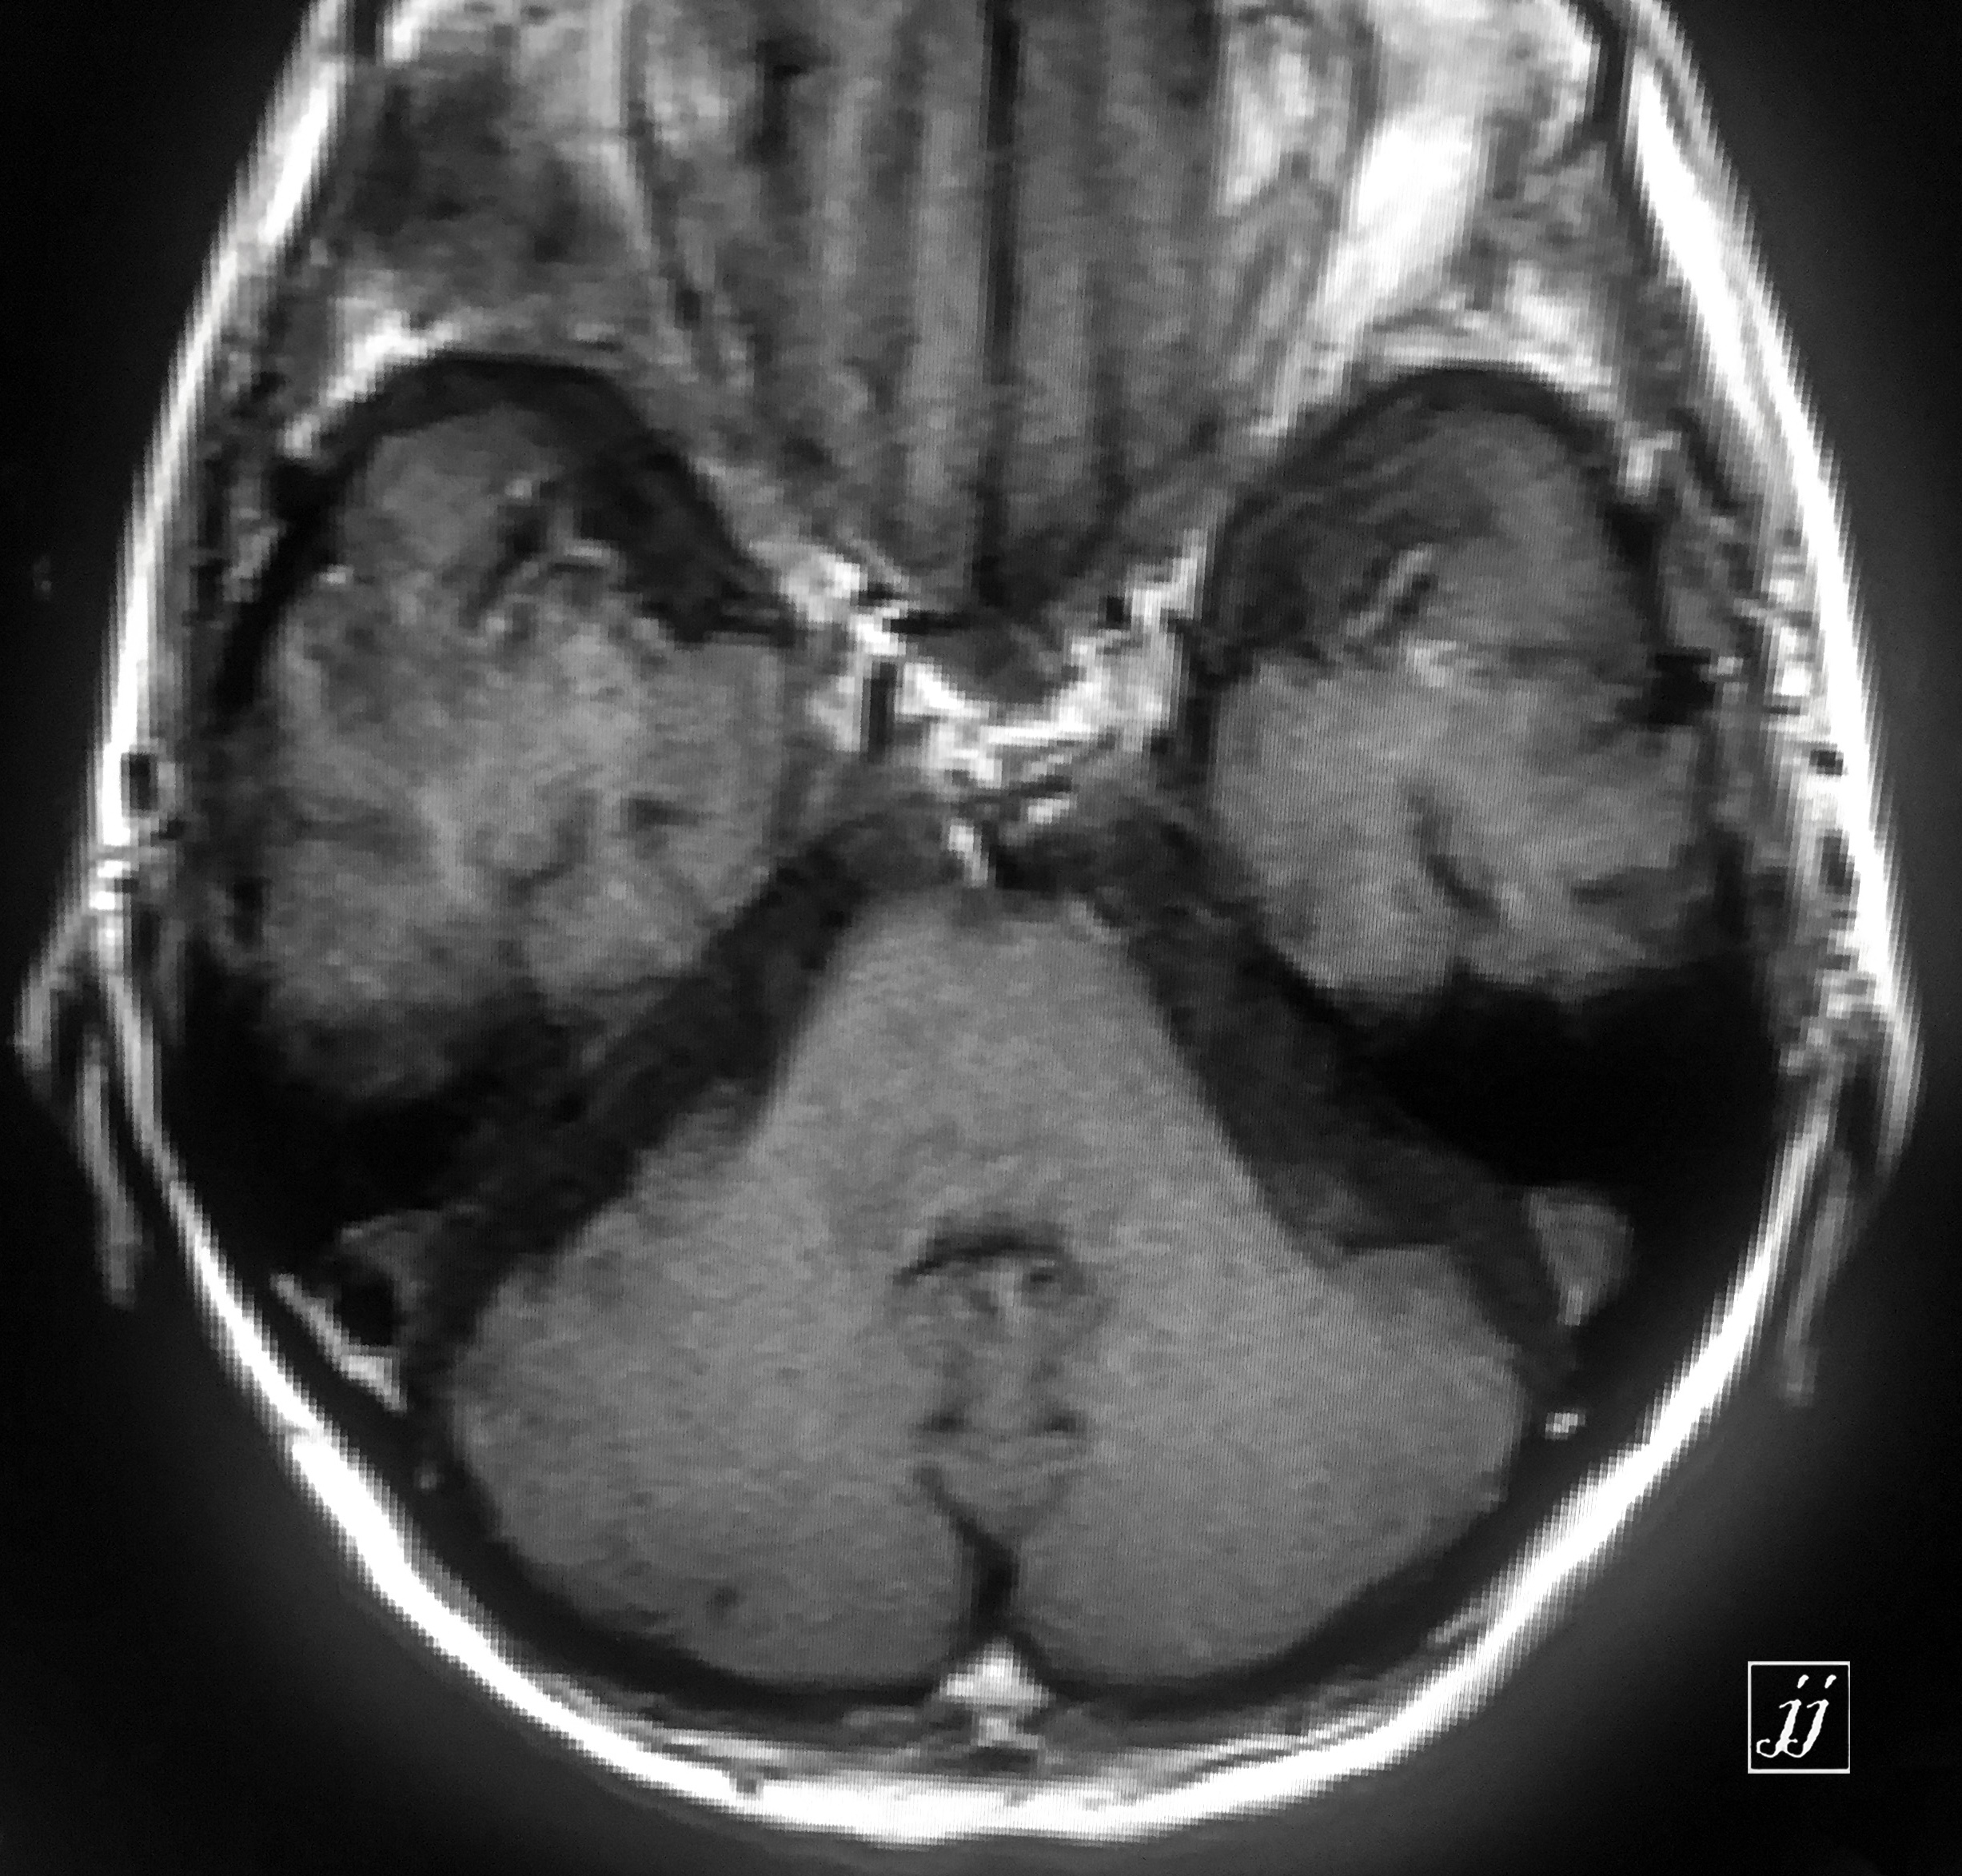

Brain- left mastoid abscess (6)